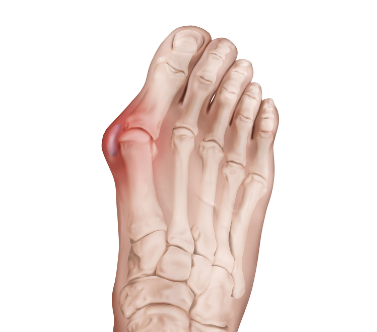

무지외반증("hallux valgus”)이란?

무지외반증은 발가락 통증을 일으킬 수 있는 특정한 상태입니다. 이는 발가락으로 통증을 유발할 수 있는 신경 주위의 조직이 두껍고 확장되는 경우 발생합니다. 이는 특히 세 번째와 네 번째 발가락 사이의 발의 앞부분에서 심한 불편함을 초래할 수 있습니다.

무지외반증의 증상

무지외반증의 흔한 증상은 다음과 같습니다.

- 발 앞부분에서 날카로운, 화끈한 통증.

- 영향을 받는 발가락에서의 저림 또는 따끔거림.

- 신발 안에 돌 또는 물체가 있다는 느낌.